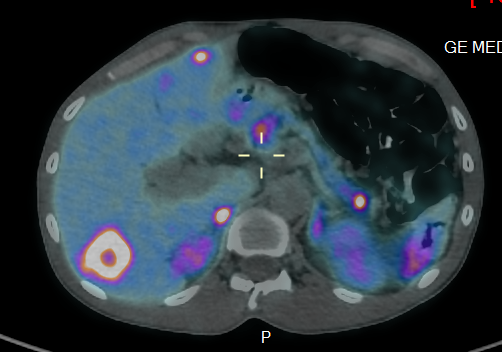

Le PET/CT au 68-Ga-DOTATOC est l'examen le plus sensible actuellement pour détecter des tumeurs neuroendocrines bien différenciées, car il détecte les récepteurs de la somatostatine (SSTR) fortement exprimés par les TNE. Cette méthode a remplacé la scintigraphie à l'Octréotide (Octréoscan), car elle offre une meilleure sensibilité et localisation de la lésion tumorale.

Pour augmenter le taux de détection de petites lésions dans l'abdomen, un scanner supplémentaire avec injection de produit de contraste peut s’avérer être nécessaire.

- Staging et re-staging de tumeurs neuroendocrines bien différenciées

- Contrôle de la thérapie

- Évaluation pour un traitement potentiel au Lutetium-177-DOTATATE